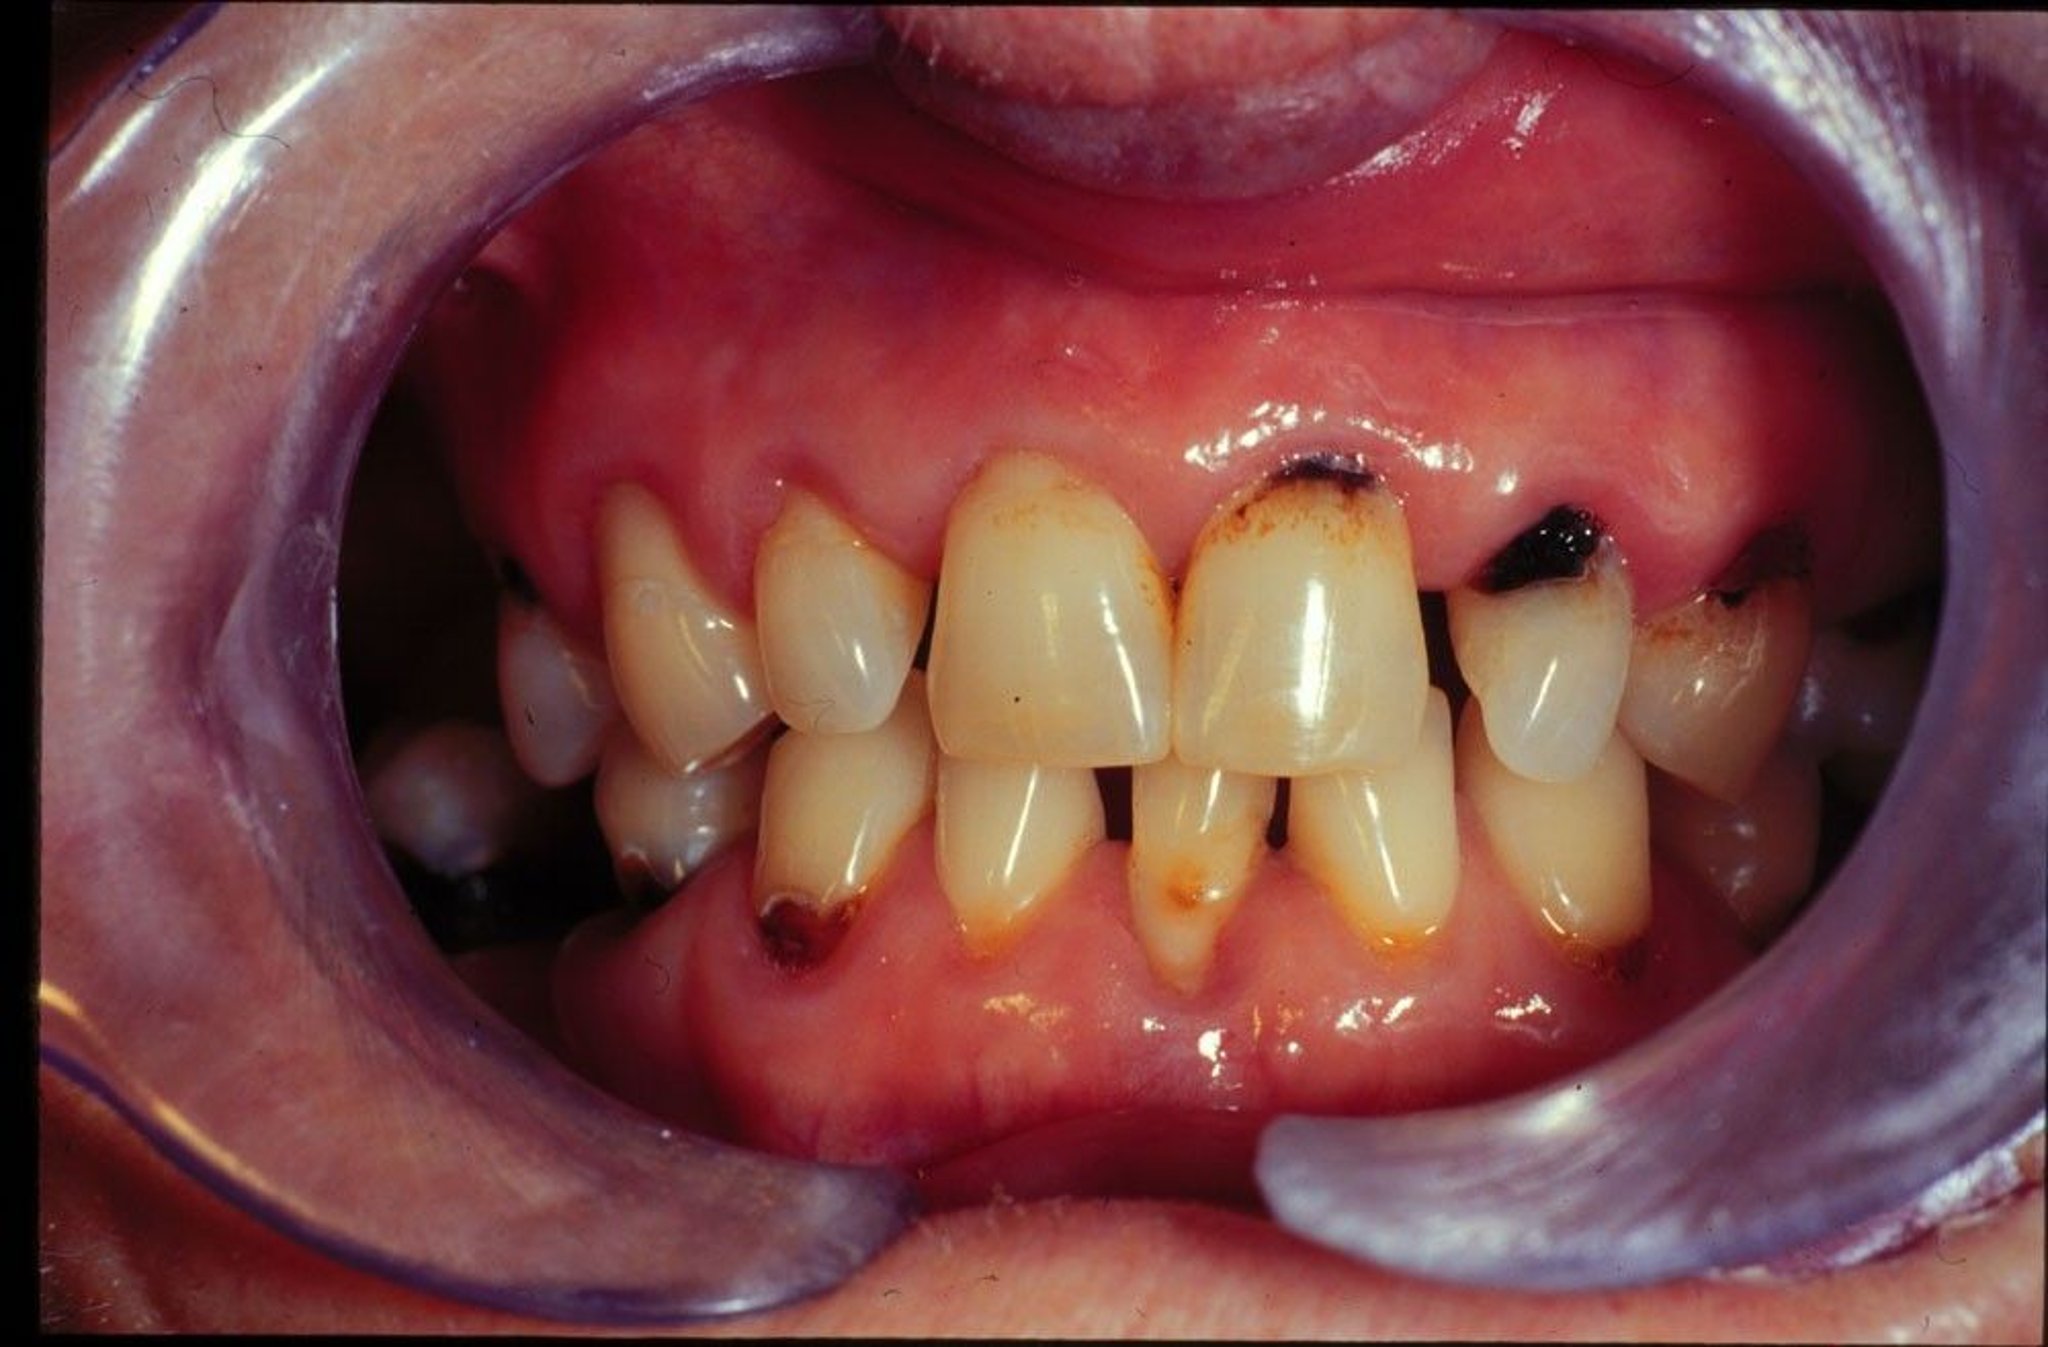

New and recurrent dental caries in a patient with dry mouth.

Image provided by Jonathan A. Ship, DMD.